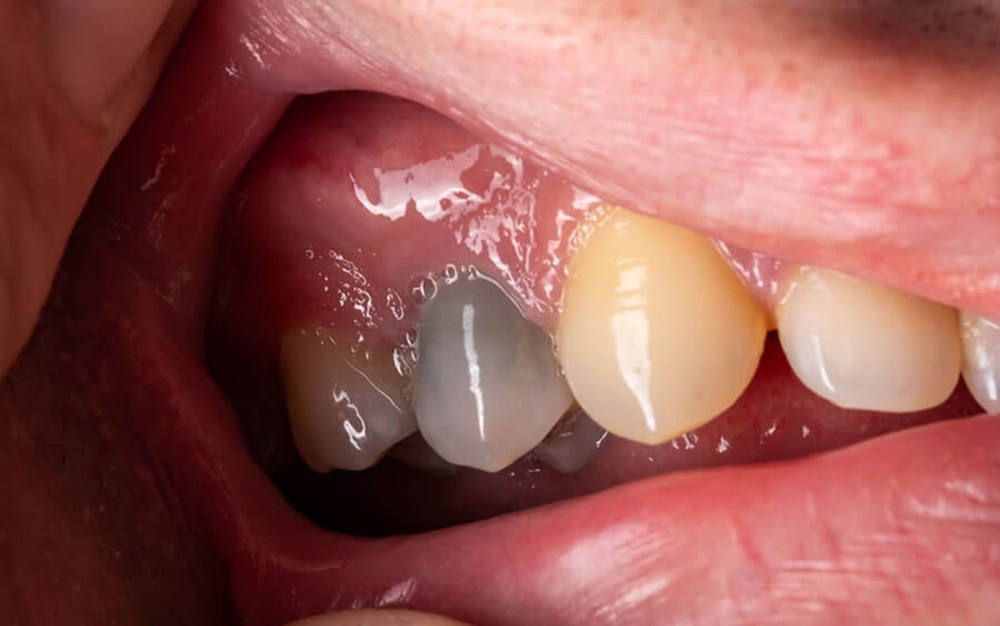

Răng chết tủy bị đổi màu, giòn và dễ vỡ

Vì tủy răng nằm trong "hộp kín" bằng men răng và ngà răng, nó không có không gian để sưng nở. Áp lực này chèn ép các sợi thần kinh, gây ra những cơn đau nhức dữ dội hoặc âm ỉ tùy mức độ. Nếu lực nén kéo dài, nguồn nuôi dưỡng bị cắt đứt hoàn toàn, tủy răng sẽ chuyển từ viêm cấp sang viêm mãn tính và cuối cùng là hoại tử vô khuẩn.

Để loại bỏ nguy cơ này, bác sĩ cần phải khảo sát kỹ phim chụp CT Cone Beam trước khi niềng, đồng thời kiểm soát được lực chỉnh nha ở trạng thái lực nhẹ và liên tục.